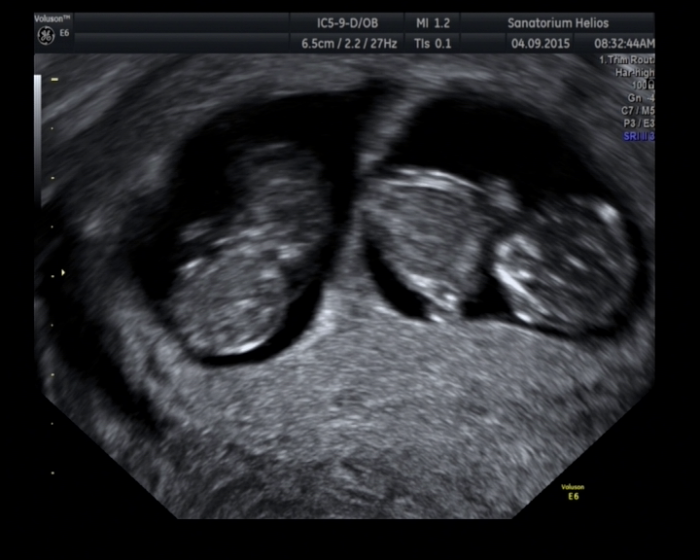

Pro Assi - ahoj Assi, posílám fotečku ze včerejšího UTZ. Jinak Máš odemě SZ